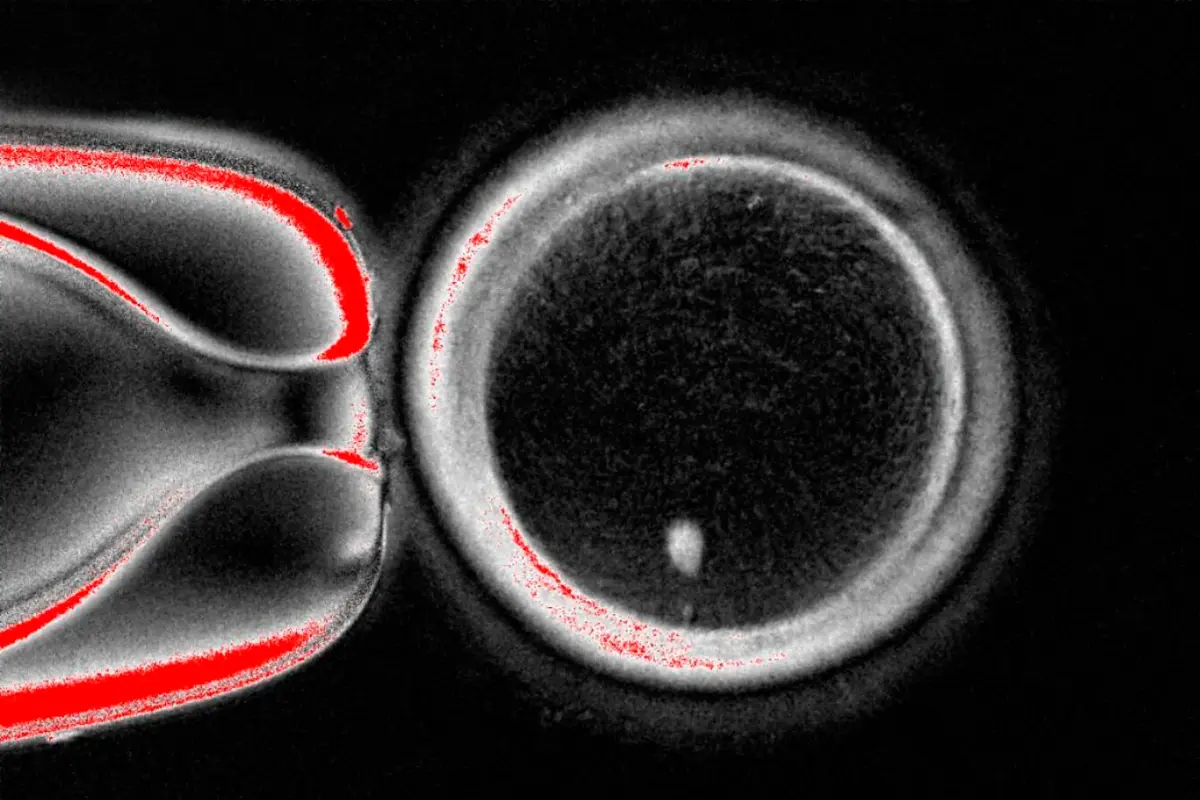

Os investigadores removeram os núcleos dos ovócitos e substituíram-nos por aqueles que foram retirados de células da pele. O objetivo era garantir que a célula pudesse ser fertilizada por um espermatozoide. Isto só é possível se ela tiver 23 cromossomas, aos quais se juntam os 23 do espermatozoide.

No entanto, como todas as células não reprodutoras, as células da pele possuem 46 cromossomas. Os investigadores removeram, por isso, metade deles, usando uma técnica a que chamaram "mitomeiose".

De seguida, tentaram fertilizar essas células com espermatozoides. Destes óvulos candidatos, cerca de dez desenvolveram-se em embriões que duraram alguns dias, uma fase teoricamente suficiente para os implantar numa paciente durante a fertilização in vitro.